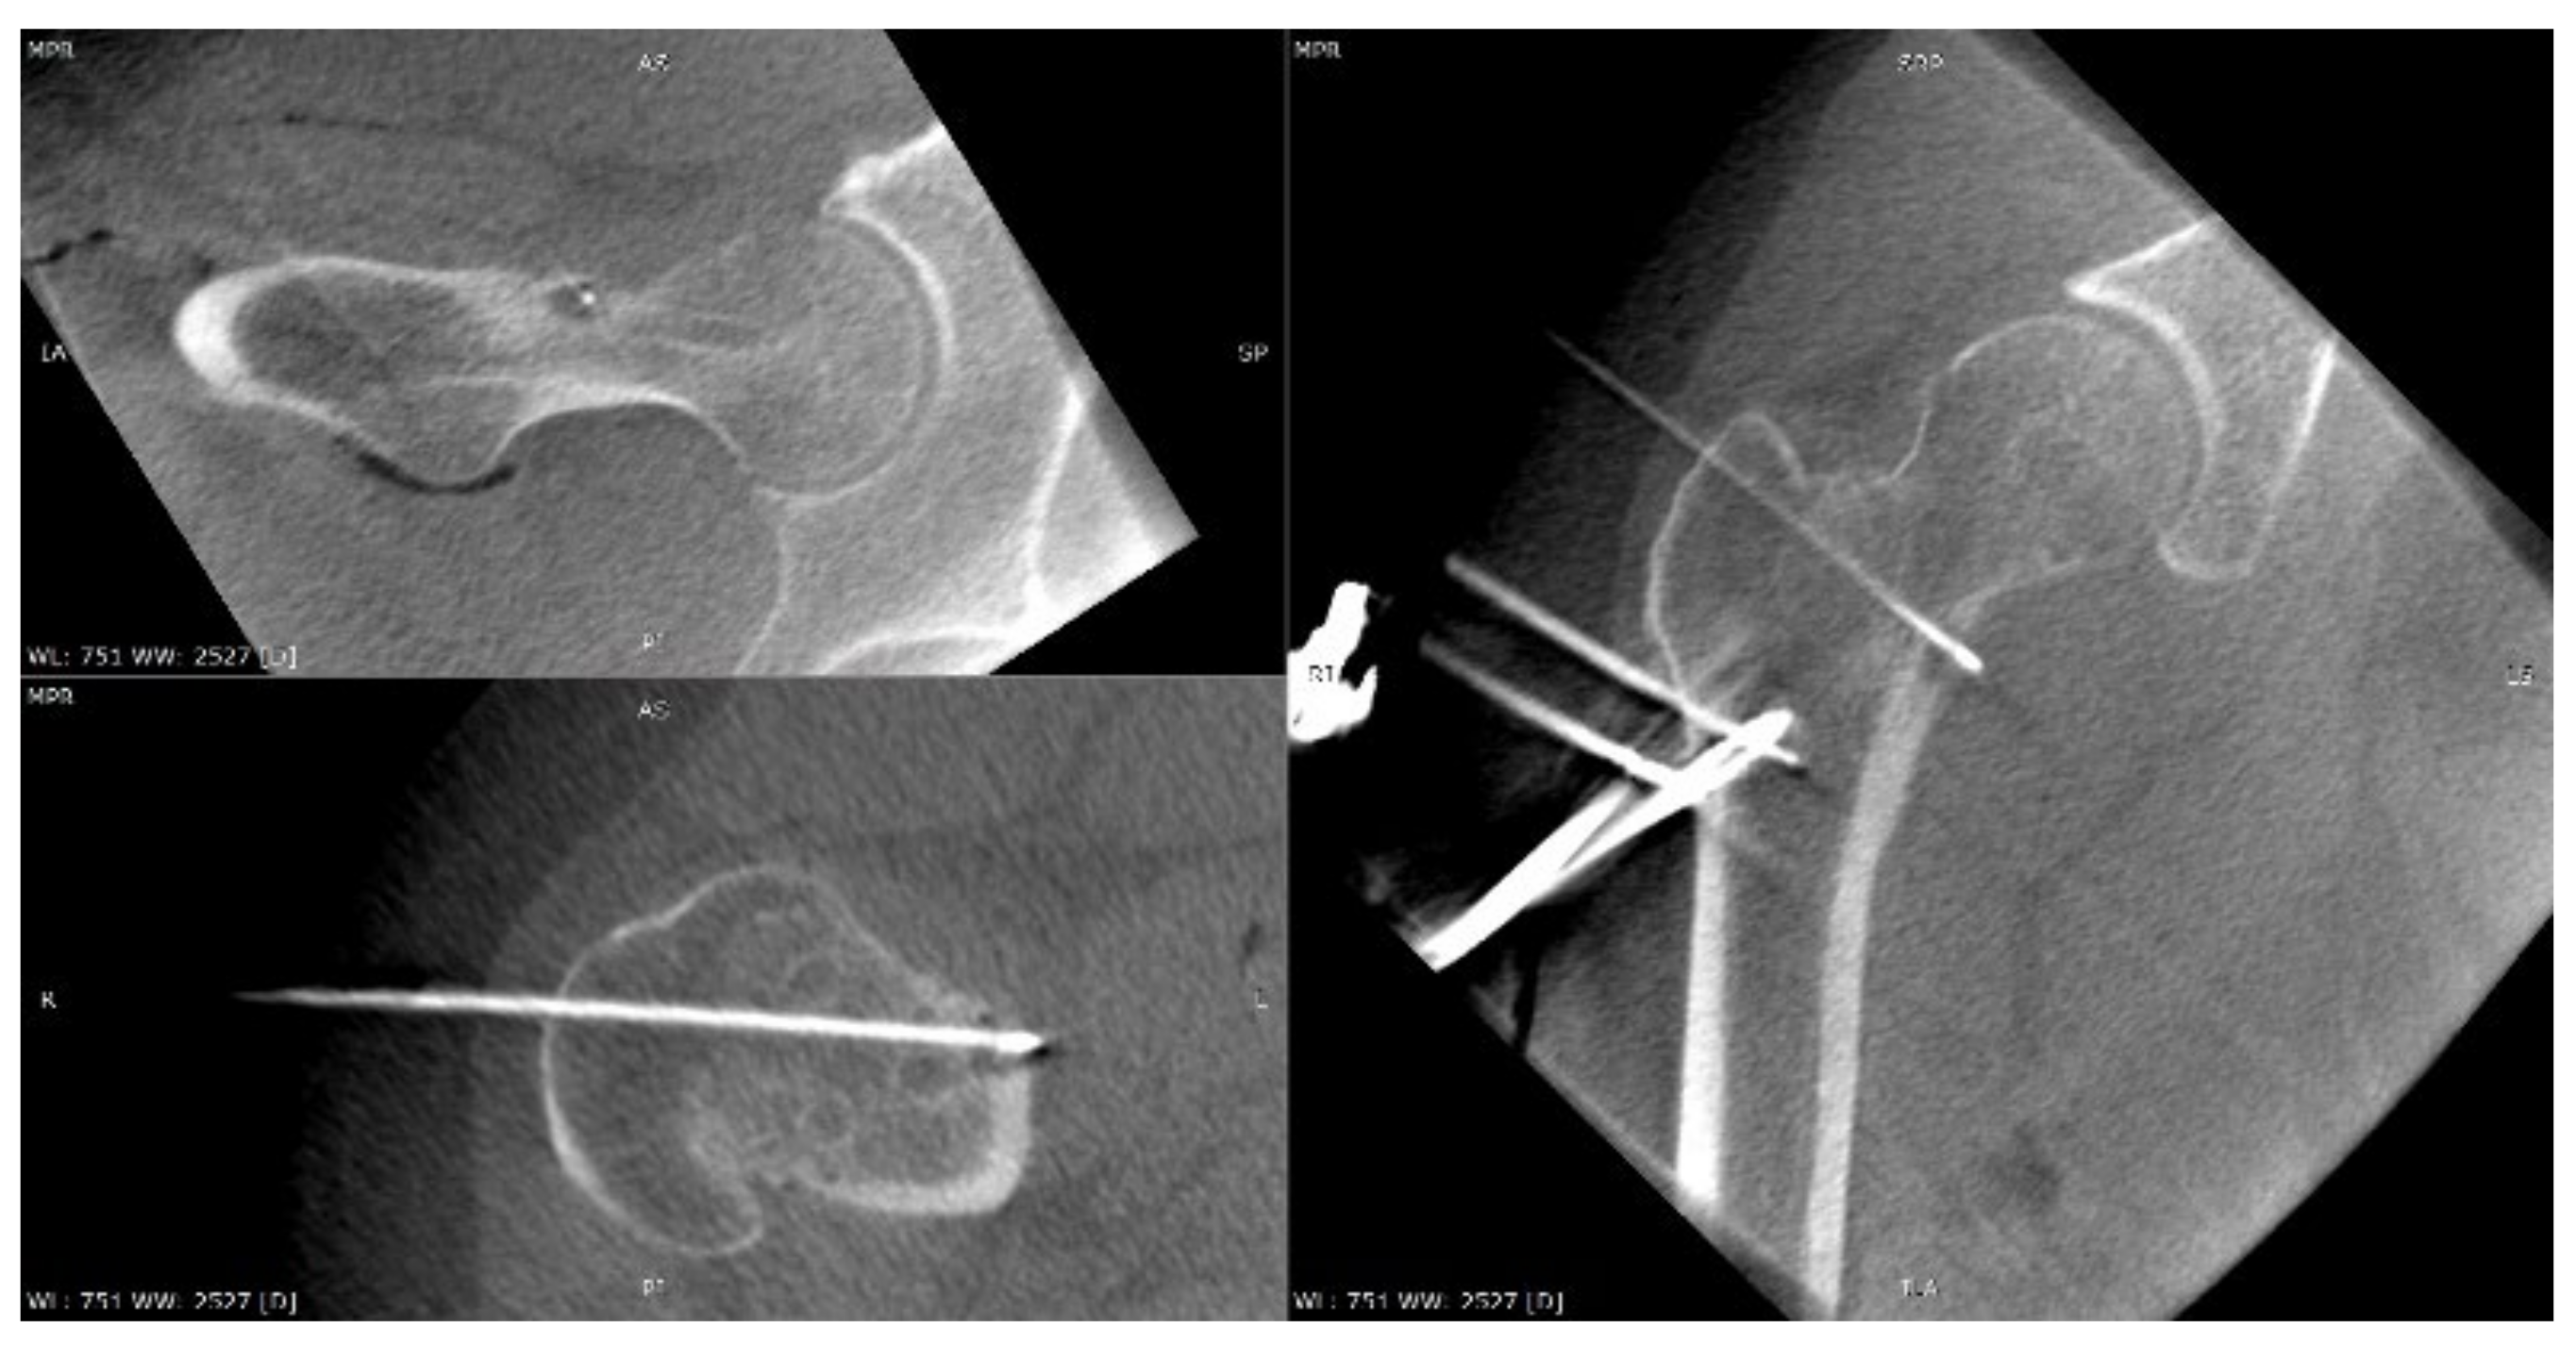

3.4. Case 4: OO Masking as a Fatigue Fracture

A 31-year-old male patient with post-exercise and night pain was seen at an orthopaedic outpatient clinic for diagnosis. The patient underwent a pelvic X-ray and an MRI scan of the right hip joint. The MRI description suggested a suspected fatigue fracture of the right femoral neck (Figure 8). The patient was qualified for surgery. Under general anaesthesia, internal stabilisation was made with three cannulated screws (Figure 9). During the following six months after surgery, the pain did not resolve. During further diagnosis, the patient had a CT scan of the hip joints. The examination revealed a focus of OO of 10 × 9 × 6 mm in the right femoral neck (Figure 10). The patient underwent thermoablation with intraoperative 3D navigation without complications (Figure 11). The VAS score of pain on the day of surgery was 7. Night and postoperative pain resolved completely. The VAS score on examination 3 months after surgery was 0. Cannulated screws were not removed.

Figure 8.

MRI scan of the hip joints; subtle changes (arrow) in the right femoral neck made suspicion of fatigue fracture, no focus of OO revealed initially.

Figure 9.

X-ray view of internal stabilisation with three cannulated screws of the right femoral neck.

Figure 10.

CT scan of the hip joints showing a focus of OO in the right femoral neck.